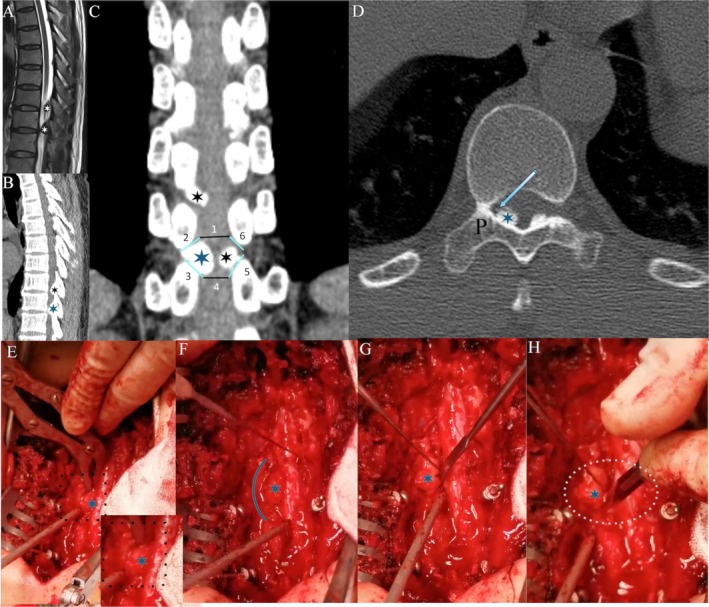

Methods: Combined with preoperative image data and intraoperative operation images, the POT decompression method was deeply analyzed. In this study, the thoracic vertebrae of sheep were taken as experimental specimens. The water sac was placed close to the joint level of the articular process to simulate the spinal cord, and the experiment was carried out by the surgical methods of PTP and POT respectively with a high-speed bur. The laser displacement sensor (LDS) was used to monitor the vibration displacement of the water sac, and the collected vibration data was divided into 0.1 s/frame (500 vibration signal data points), which were used to calculate the curvature change of the vibration displacement curve. The Wilcoxon rank sum test was used for statistical analysis. Milling parameters for the high-speed bur were set to: milling depth 0.5 mm, milling speed 0.5 mm/s, milling angle 45°, and spherical bit size 4 mm.

Results: Combining the detailed preoperative image data and intraoperative images of key operations, the study first provides a detailed description of the surgical steps for safe posterior thoracic decompression via the POT. Then, based on Euler-Bernoulli beam theory, the vibration of the "spinal cord" under different surgery pathways (POT and PTP) in posterior thoracic decompression was further studied. The statistical analysis showed that the vibration amplitude and curvature value of the vibration curve of POT and PTP were significantly different (p < 0.05). As the milling position approached POT, the amplitude and curvature values also decreased gradually.